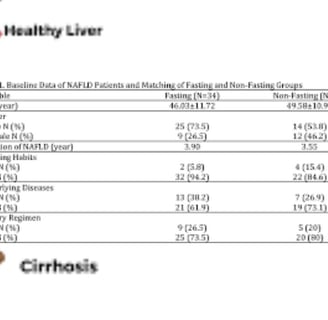

يعتبر الصيام المتقطع خيارًا ممتازًا لمرضى الكبد الدهني، حيث أثبت فعاليته في تقليل الوزن وكتلة الدهون ومحيط الخصر، بالإضافة إلى تحسين مستويات ALT والأنسولين ومقاومة الأنسولين، وزيادة حساسية الأنسولين لدى مرضى السمنة والكبد الدهني غير الكحولي.